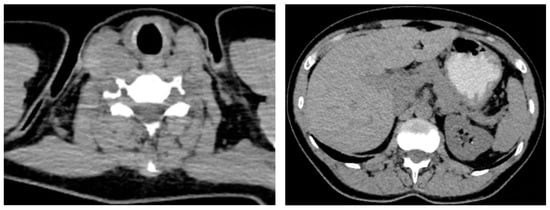

| Confirmation of the endocrine tumor/cancer | Yes (+2/10 cervical lymph nodes invasion) | Yes (bilateral) | Yes (left inferior parathyroid tumor) |

| Age at diagnosis | 31 years (+ RET testing at 31 years) | ||

| Hormonal assays before surgery | Calcitonin = 304 ng/mL (normal: 1–4.8) | Plasma metanephrines = 300 pg/mL (normal: 0–90) Plasma normetanephrines = 400 pg/mL (normal: 20–200) | PTH = 122 pg/mL (normal: 15–65) Total serum calcium = 11.4 mg/dL |

| Surgery | Yes (synchronous total thyroidectomy, neck lymph nodes dissection and selective removal of a single parathyroid tumor) | Yes (synchronous bilateral adrenalectomy) | Yes |

| Age at the moment of surgery | 31 years | ||

| Confirmation of the endocrine tumor/cancer | Yes (no lymph nodes invasion) | Yes (bilateral) | No |

| Age at diagnosis | 30 years (+RET testing at 30 years) | 32 years (left adrenal), respectively, 38 years (right adrenal) | No |

| Hormonal assays before surgery | Calcitonin = 74 ng/mL (normal: 1–4.8) | Plasma metanephrines = 148 pg/mL (normal: 0–90) Plasma normetanephrines = 78 pg/mL (normal: 20–200) | No |

| Surgery | Yes (total thyroidectomy + neck lymph nodes dissection) | Yes (asynchronous bilateral laparoscopic adrenalectomy) | No |

| Age at the moment of surgery | 30 | 32, respectively, 38 years | No |